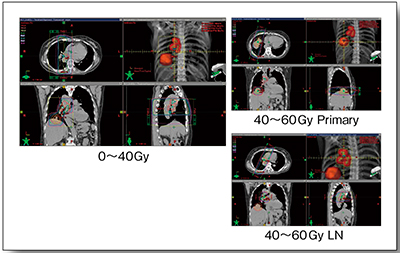

症例1は,76歳,女性。小細胞肺癌(cT3N1M0,右下葉原発)のため化学療法が行われたが,制御不良であったため放射線治療(CBDCA+VP-16併用,60Gy/30回)が施行された。はじめに4D-CTにてITVを決定するが,4D-CTから得られる呼気相と吸気相の画像をPET画像とフュージョンすると,全相においてほぼ一致していることが認められる(図4)。ITVはすでに決定しているので,これを基にPTVを設定すれば,動きのある領域の腫瘍であっても,きわめて高精度な照射が可能となる。図5は実際の治療計画である。肺がんの場合,主腫瘍とリンパ節転移は呼吸による動きが異なるが,4D-CT画像を用い,それぞれに最適なフィールド設定が可能であり,適切な照射が可能となる。本症例は,治療1か月後の画像にて著明な腫瘍縮小が認められた。

図5 症例1:放射線治療計画